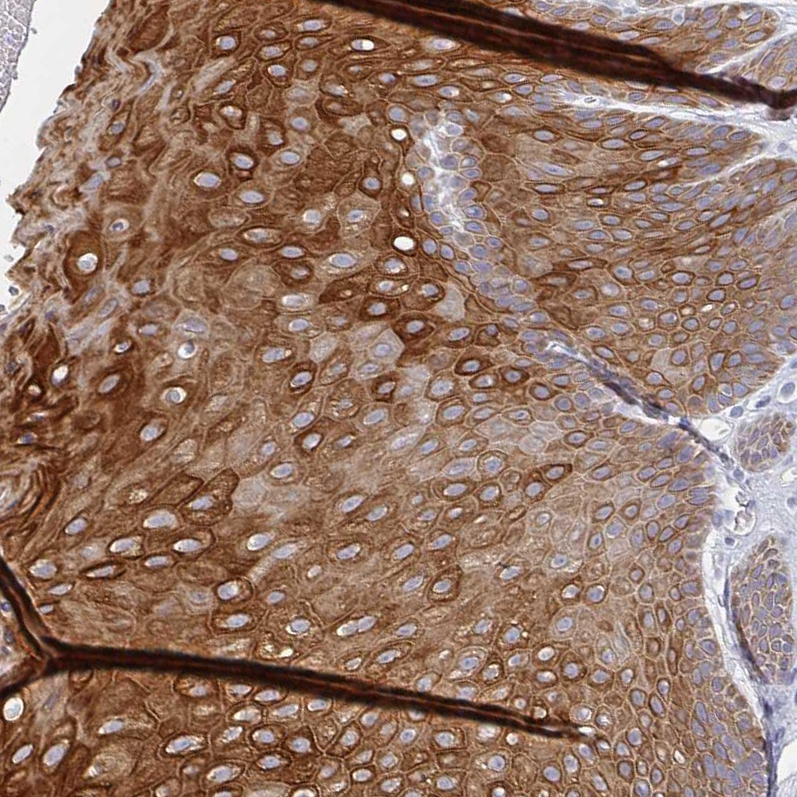

Immunohistochemistry analysis in human skin and cerebral cortex tissues using HPA053343 antibody. Corresponding RHOV RNA-seq data are presented for the same tissues.